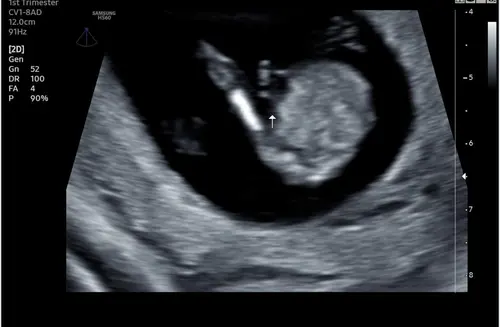

Ik denk dat je dit het beste even bij je verloskundige kan navragen. Ik kan best aardig zelf een echo maken, ben niet opgeleid voor baby's hoor, maar ik vind dit beeld erg lastig zo stilstaand.

Mij lijkt het in ieder geval geen geslacht want dan zou je meer been moeten zien denk ik. Dan eerder de navelstreng maar vind de organen niet duidelijk dan weer dat het om de buik gaat en niet mooi rond genoeg.

Nee sorry maar denk echt dat het sowieso geen geslacht is. Met 13 weken kijken ze daar meestal ook niet naar omdat de kans dat ze het mis hebben erg groot is. En je zou dan maar één been zien en dat is raar.

Zoals ik hem zie is dit een zij aanzicht waarbij het witte een been is, en het pijltje dus ter hoogt van de navel is (ter aanduiding waar de navelstreng uit de buik komt)

was dit met de 13 weken echo? Want dan zou dat het wel verklaren aangezien ze er een pijltje gezet hebben

Het is (zover ik zie) in elk geval geen echobeeld van de onderkant, dan zou je 2 benen zien zoals op het beeld wat eerder al gereageerd is in een foto.

Met de 13 weken echo kijken ze ook niet naar geslacht dus daar duidt het pijltje sowieso niet op, al zouden ze het kunnen zien, wat op deze termijn niet betrouwbaar is, zouden ze er geen pijltje bij gezet hebben.